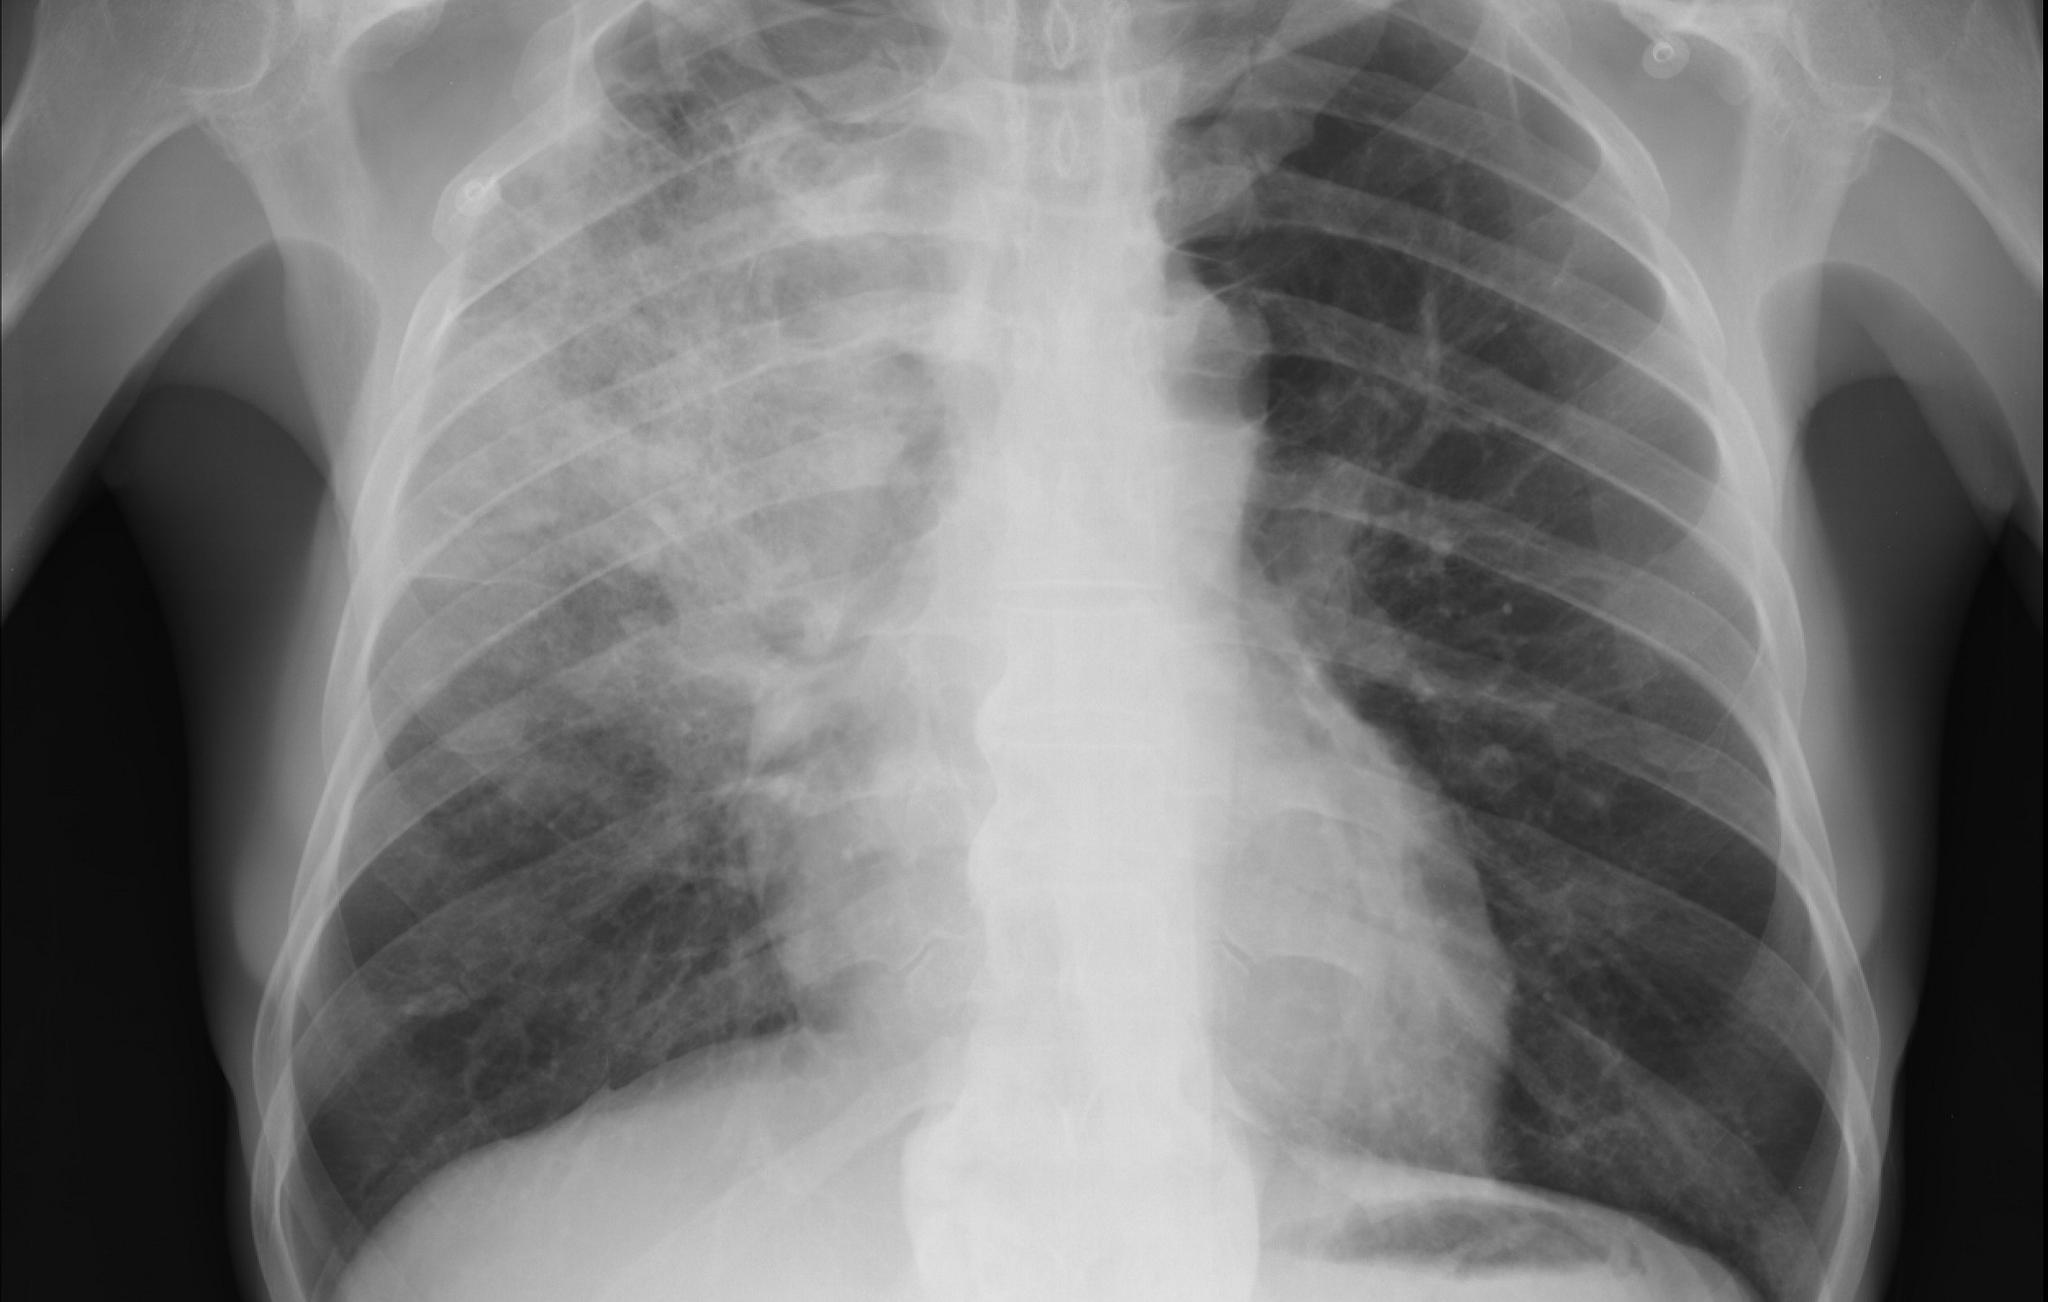

Segundo Sarmet, no entanto, o exame mais recomendado no primeiro contato com o paciente é o raio-x de tórax. “O paciente chegou com síndrome gripal, tem que ser examinado quanto à febre e à saturação sanguínea. Depois, o primeiro exame de imagem a ser feito é um raio-x de tórax”, observou. Ele destacou que pacientes com saturação abaixo de 93% devem ficar em observação. "Caso já chegue com menos do que isso, será encaminhado à UTI, mas antes, fará a tomografia para identificar se tem doenças associadas como H1N1 e tuberculose”, explicou. Na UTI, segundo Sarmet, o acompanhamento também deve ser feito por raio-x diário.

Coordenador da comissão científica do CBR, Waldair Muglia destacou por fim que, em situações de escassez de testes laboratoriais, a tomografia pode ser usada desde que sempre acompanhada de dados clínicos e epidemiológicos, para evitar diagnóstico cruzado de Covid-19 com outras doenças. “ Os achados não são específicos da Covid-19 e podem se sobrepor aos de várias outras patologias, como H1N1 e pneumonias virais”, disse.